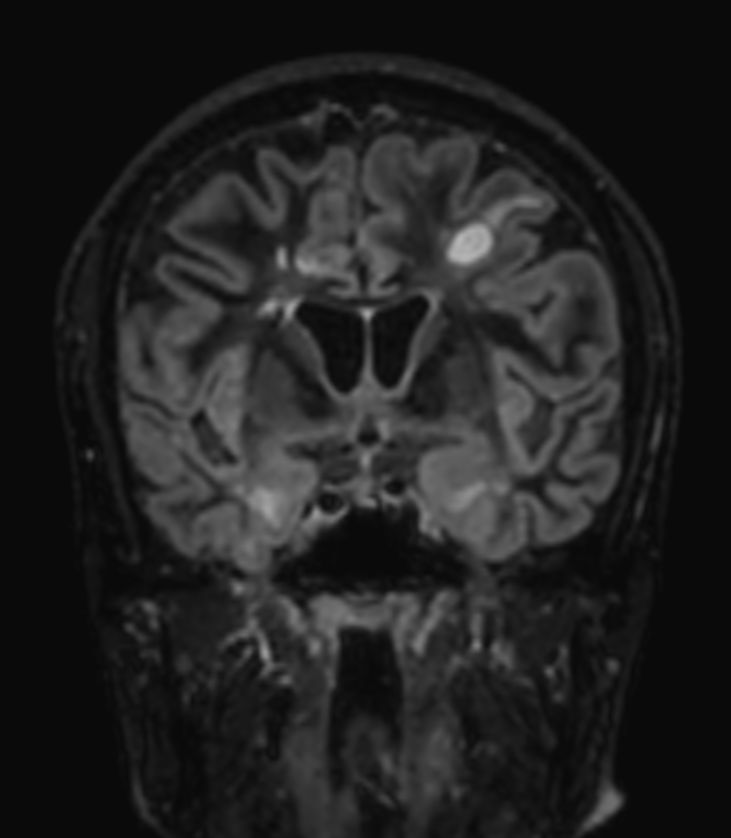

3D T2w FLAIR BrainVIEW Compressed SENSE

3D T2w FLAIR BrainVIEW (reformat) Compressed SENSE